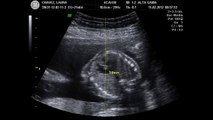

Ecografia Morfológica 24 semanas Vinicius